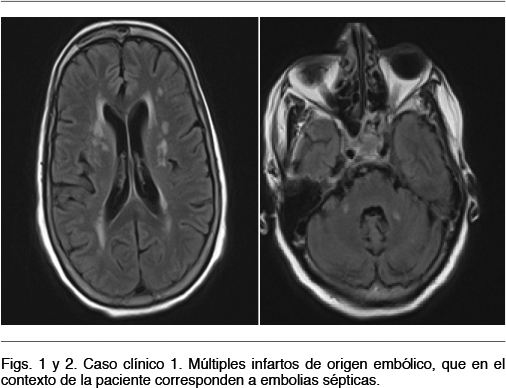

Resonancia nuclear magnética encefálica: infartos cerebelosos bilaterales y frontales. Figuras 1 y 2.

Nuevo ETE: FEVI 45%. Vegetación mitral perforada a nivel de la valva posterior con insuficiencia severa. Pequeña vegetación sobre válvula aórtica. Figura 3